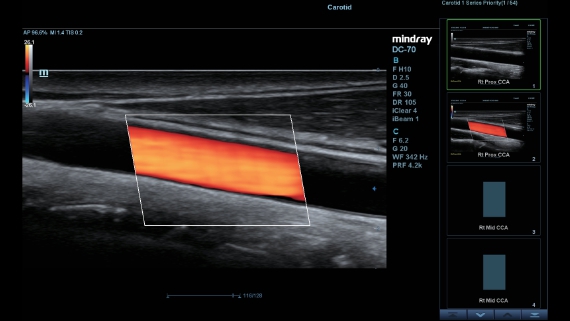

–ú–Ω–æ–≥–æ—Ñ—É–Ω–∫—Ü–∏–æ–Ω–∞–ª—å–Ω–∞—è —Å–∏—Å—Ç–µ–º–∞ DC-60 Exp —Å X-Insight –ø—Ä–µ–¥—Å—Ç–∞–≤–ª—è–µ—Ç —Å–æ–±–æ–π –∫–æ–º–ø–ª–µ–∫—Å–Ω–æ–µ —Ä–µ—à–µ–Ω–∏–µ, –∫–æ—Ç–æ—Ä–æ–µ –ø–æ–º–æ–≥–∞–µ—Ç —É–ø—Ä–∞–≤–ª—è—Ç—å –ø–æ–≤—Å–µ–¥–Ω–µ–≤–Ω–æ–π –∫–ª–∏–Ω–∏—á–µ—Å–∫–æ–π –ø—Ä–∞–∫—Ç–∏–∫–æ–π —Å –ª–µ–≥–∫–æ—Å—Ç—å—é –∏ —É–≤–µ—Ä–µ–Ω–Ω–æ—Å—Ç—å—é.

–û—Å–Ω–æ–≤—ã–≤–∞—è—Å—å –Ω–∞ –≥–ª—É–±–æ–∫–æ–º –ø–æ–Ω–∏–º–∞–Ω–∏–∏ –ø–æ—Ç—Ä–µ–±–Ω–æ—Å—Ç–µ–π –∫–ª–∏–µ–Ω—Ç–æ–≤, –∫–æ–º–ø–∞–Ω–∏—è Mindray —Ä–∞–∑—Ä–∞–±–æ—Ç–∞–ª–∞ —Å–∏—Å—Ç–µ–º—É DC-60 Exp —Å X-Insight, —á—Ç–æ–±—ã –æ–±–µ—Å–ø–µ—á–∏—Ç—å –≤—ã—Å–æ–∫—É—é –ø—Ä–æ–∏–∑–≤–æ–¥–∏—Ç–µ–ª—å–Ω–æ—Å—Ç—å –∏ —Ç–æ—á–Ω–æ—Å—Ç—å –≤–∏–∑—É–∞–ª–∏–∑–∞—Ü–∏–∏ –≤–∫—É–ø–µ —Å –Ω–∞–≥–ª—è–¥–Ω–æ—Å—Ç—å—é, –∏—Å–∫–ª—é—á–∏—Ç–µ–ª—å–Ω–æ–π –∏–Ω—Ç–µ–ª–ª–µ–∫—Ç—É–∞–ª—å–Ω–æ—Å—Ç—å—é –∏ –æ–≥—Ä–æ–º–Ω—ã–º –æ–ø—ã—Ç–æ–º.